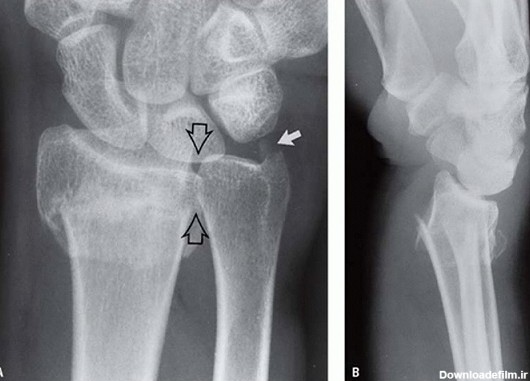

شکستگی های استخوانهای مچ دست شایع در اندام فوقانی به حساب می آید که در اثر زمین خوردن و هایپراکستنشن مچ دست بیش از 95 درجه و تحت فشار قرار گرفتن اسکافویید.

استخوان اسکافوئید (ناوی)،یکی از استخوان های کوچک مچ دست است. شکستگی اسکافویید اغلب در پی افتادن بر روی دست باز شده به سمت بیرون رخ می دهد. علائم شکستگی استخوان اسکافوئید معمولاً درد و حساسیت دقیقا در ناحیه ابتدایی انگشت شست است. وقتی می خواهید چیزی را فشار دهید یا بگیرید، ممکن است این علائم […]